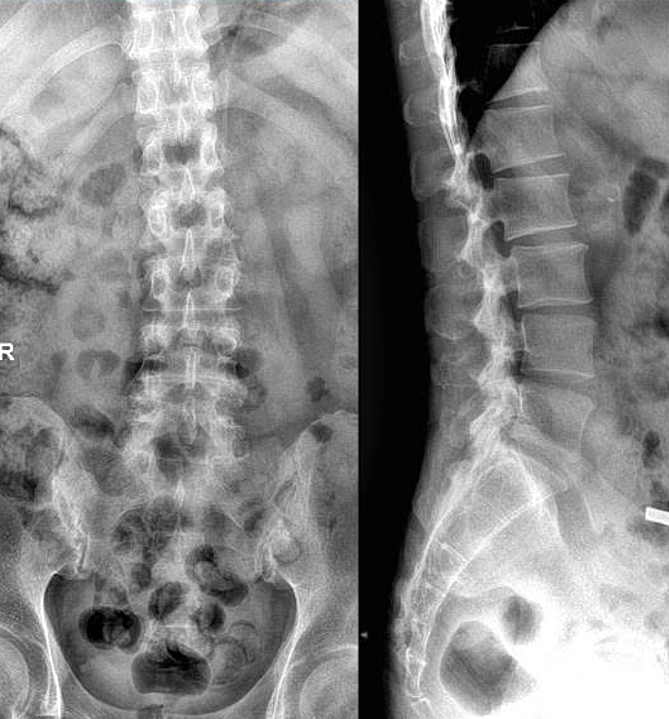

PGS Hoa nhận thấy ngoài triệu chứng gout, người bệnh còn đau nhiều dọc cột sống, khớp vai hai bên, nhất là ban đêm gây rối loạn giấc ngủ, viêm và khô da tăng khi thay đổi thời tiết, không đáp ứng tốt với thuốc trị gout. Phim chụp X-quang cho thấy khe khớp cùng chậu mờ, đặc xương hai bên, chụp cộng hưởng từ MRI ghi nhận phù tủy xương bờ khớp cùng chậu, PGS Hoa chẩn đoán anh Quang mắc viêm khớp cột sống chồng lấp bệnh gout.

Phim chụp X-quang của anh Quang cho thấy biểu hiện viêm khớp cột sống. Ảnh: Bệnh viện Đa khoa Tâm Anh